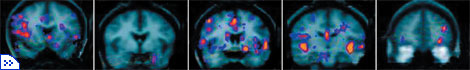

Томографические изображения мозга кокаинистов. |

Хотя основные представления о деятельности мозговой системы вознаграждения сложились в результате экспериментов на животных, исследования, проведённые за последние 10 лет методами нейровизуализации, показали, что аналогичные нервные структуры контролируют поведение, связанное с естественным или наркотическим вознаграждением, и у человека. С помощью магнитно-резонансной и позитронной эмиссионной томографии было установлено, что предложение понюхать кокаин вызывало у наркоманов рост нейронной активности в прилежащем ядре. Точно так же это ядро (а кроме него — миндалина и некоторые области коры) отреагировало и на демонстрацию испытуемым видеоклипа, где кокаин нюхали другие люди. А у заядлых игроков эти области мозга активизировались в ответ на предъявление фотографий игровых автоматов. Таким образом, можно предположить, что нервный путь ВОП—прилежащее ядро играет важную роль в развитии болезненного привыкания и ненаркотической зависимости.